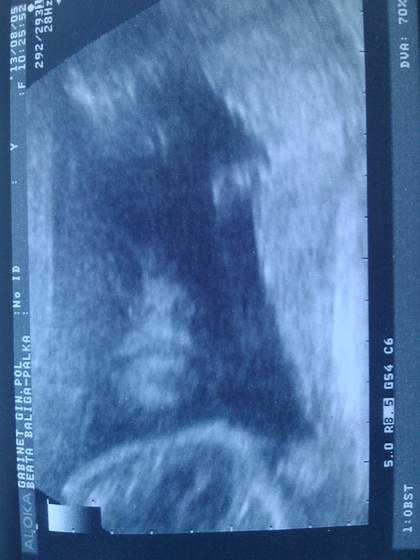

wiec po 3D u nas wszystko dobrze, maly wazy 600g, czyli w dwa tygodnie przybral ok 100g.

Pomiary sa ok, serce nerki i pluca w porzadku. Maly jest jak na 23.6 ale to jest tez w normie. Nosek ma 0,68 i ponoc moglby miec dluzsza kosc ale jest ok. Nic nie zaniepokoilo Pana dr.

a oto moj synalek :-) troche nudza go te badania chyba

a fotka faktycznie bardzo wyrazna